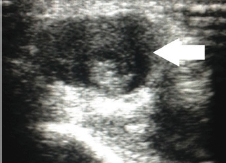

Figure 2: Ultrasonography without Doppler demonstrating thrombosis in the distal radial artery (white arrow).

A 69 years old man with right wrist pain and functional limitations for 06 months. Finkelstein, Tineland Phalentests were negative. Important edema in the wrist and hand at physical examination (Figure 1). Ultrasonography demonstrated pseudo aneurysm with thrombosis in the distal radial artery (Figures 2 & 3).